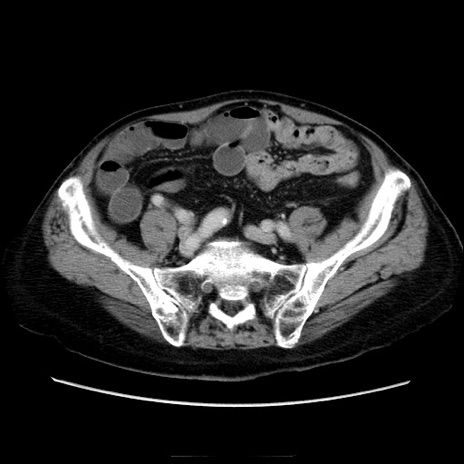

症例21(横断像)

【症例】70歳代男性

【主訴】腹痛

【現病歴】肝硬変・肝細胞癌にてかかりつけの方。約9時間前に食後より腹痛出現。症状が徐々に増悪し、嘔吐出現したため来院。

【既往歴】肝硬変、肝細胞癌(RFA、TACE後)

【身体所見】意識清明、表情苦悶様、BT 36℃、BP 129/78mmHg、P 88bpm、SpO2 97%(RA)、右上腹部から心窩部にかけて圧痛あり、反跳痛なし、筋性防御あり。

【データ】WBC 5800、CRP 0.16